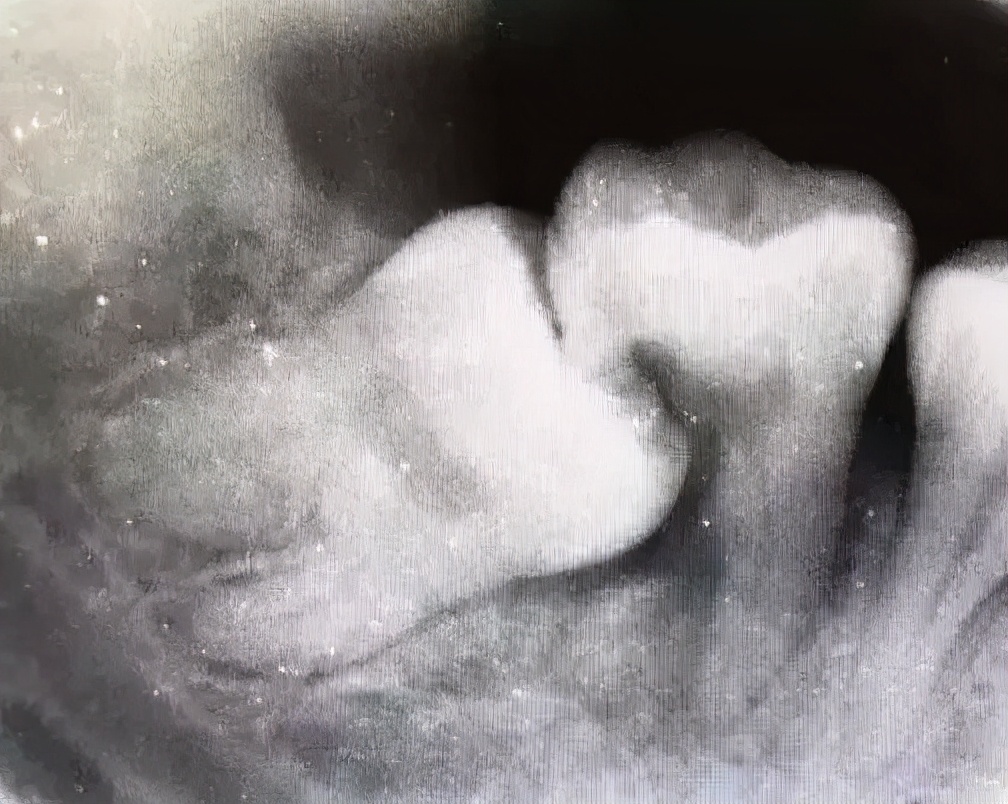

下图的智齿已经完全长出了,也已经蛀掉了,所以这种情况就要赶紧找牙医去拔掉,否则还会连累第二磨牙也一起蛀牙,那就更麻烦了。